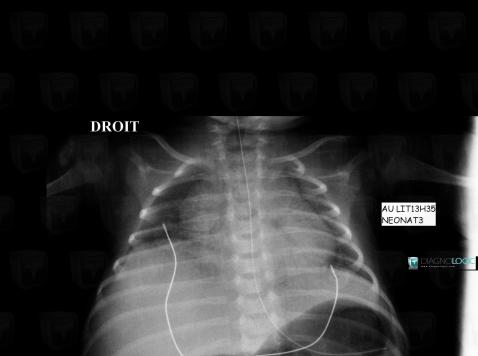

Paralysie-nerf phrénique, Diaphragme, Radio

Voici les informations spécifiques à l'image clé ci dessus:

- Diagnostic Paralysie du nerf phrénique, Localisation(s) Diaphragme, comportant les gammes Elévation de coupole unilatérale